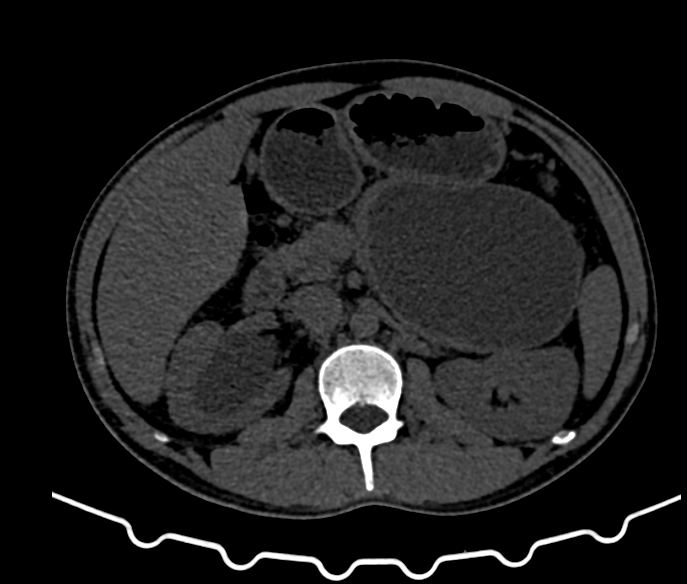

Pancreatic Findings:

- Lesion: Well-defined rounded cystic hypoattenuating lesion, measuring approximately 11.3 x 8.3 x 7.8 cm (TRA x CC x AP).

- Location: Occupies the neck, body, and tail of the pancreas; inferior to the greater curvature of the stomach, anteroinferior to the spleen, and anterior to the upper pole of the left kidney.

- Impact: Abutting the greater curvature of the stomach and displacing the splenic vessels.

- Diagnosis: CT features suggestive of a pseudocyst of the pancreas.

- Large Pancreatic Pseudocyst